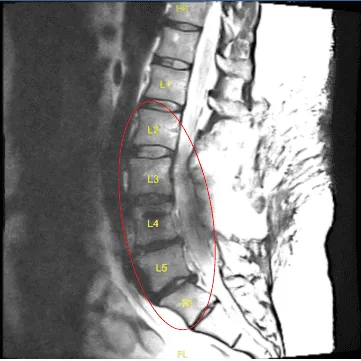

The patient was complaining of pain in both lower extremities. They had a history of L3 to S1 fusion done by another physician. Imaging studies showed good fusion mass from L3 to S1 but compression over L2-L3 segment with bilateral neural foraminal compression of L3 along with bony island formation over L3-L4 region with foraminal compression.

Status post posterior decompression the spinal canal from L2 through S1